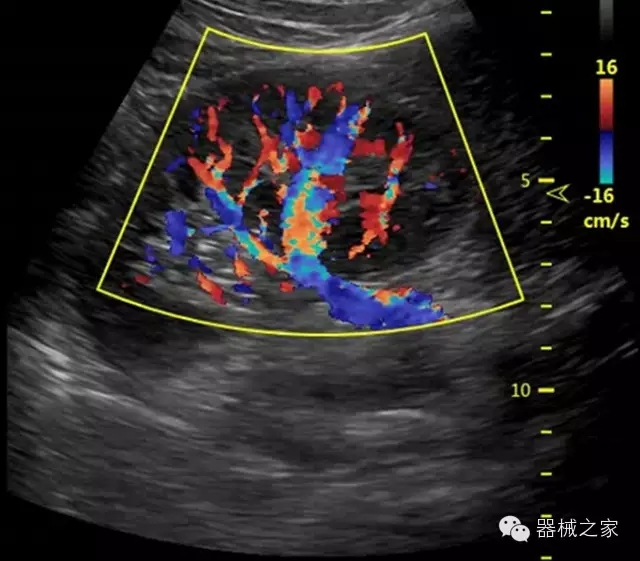

·智能微血流成像技術(shù):智能微血流捕捉技術(shù)可以提取出隱藏在背景噪聲中的弱血流信號,大大提高低速血流的敏感性;

·移植S40高端臺式彩超高端平臺技術(shù),滿足超聲科腹部、淺表、婦產(chǎn)科、心血管、肌骨等應用,提供超聲科完美解決方案;